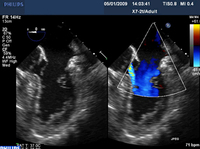

Apical 4-chamber view of 1-2+ posteriorly directed mitral regurgitation

From the collection of Samir Kapadia and Mehdi H. Shishehbor